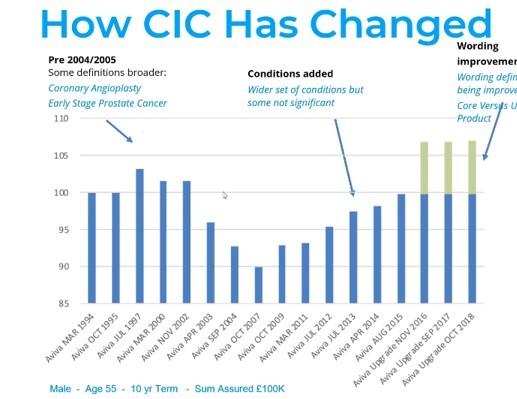

When we are protecting ourselves and our families against critical illnesses its good to know how protection works. […]